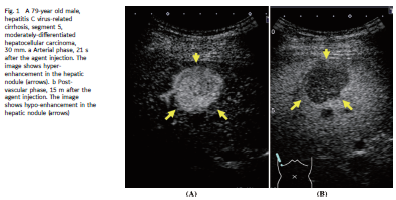

02 影像学分期 造影剂注射后的10-20s 至30-45s 为动脉相,30–45s 至120 s 为门静脉期,120s 之后为后期,而在 Sonazoid 增强造影超声中, 10分钟之后为血管后期,这个阶段的显像与kupffer细胞吞噬造影剂有关。

03.3 肝脏局部病变的特征 动脉相显示富血供征象是肝细胞性肝癌的一个典型特征。

03.4 病灶的分化程度 S-CEUS检查中,血管相对病灶分化程度的鉴别比血管后期更为有效。有研究表明,低分化肝细胞性肝癌的“快出”征象较中度分化和分化良好的肝细胞性肝癌更为常见。(1分钟时,低分化肝细胞性肝癌的vs中度分化肝细胞性肝癌,p=0.0117, 低分化肝细胞性肝癌的vs分化良好肝细胞性肝癌,p=0.0003)。此外,S-CEUS检查对病灶分化程度的评估也优于EOB-MRI。